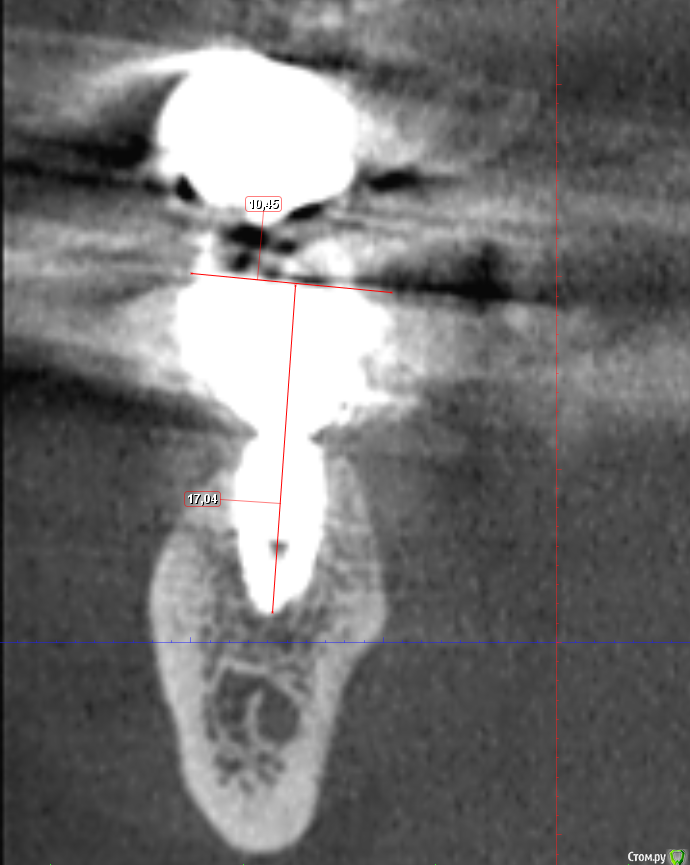

Sergiosse Опубликовано 26 сентября, 2017 Автор Поделиться Опубликовано 26 сентября, 2017 Решил продырявить коронку,я предварительно отправил на компьютерную томограмму, чтобы узнать проекцию выхода Шахты винта на жевательную поверхность. Как сделаю отпишусь. Ссылка на комментарий

Sergiosse Опубликовано 28 сентября, 2017 Автор Поделиться Опубликовано 28 сентября, 2017 снимок помог за сверлится в правильном месте, без него отверстие было бы в два раза шире чем нужно. Поставил новый Винт отверстие запломбировал. 3 Ссылка на комментарий